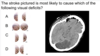

What imaging is used in this picture? [1]

dopamine transporter (DaT) - DaT scan